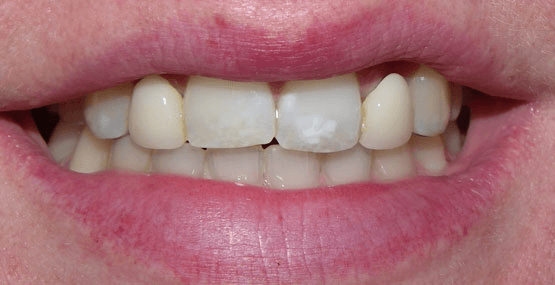

Ultimately, we chose to do two separate bridges out of an all-ceramic material, bonded only to the canines on each side. E.max lithium disilicate bridges from Ivoclar Vivadent 13-X and X-23, cemented by first air abrading the teeth, acid etching with Bisco’s Uni-etch 32% H3PO4 (aq) with BAC, and finally bonding in with Calibra Adhesive Resin cement as per recommended protocol. The results showcase a much more natural smile that’s both brighter and more resilient.